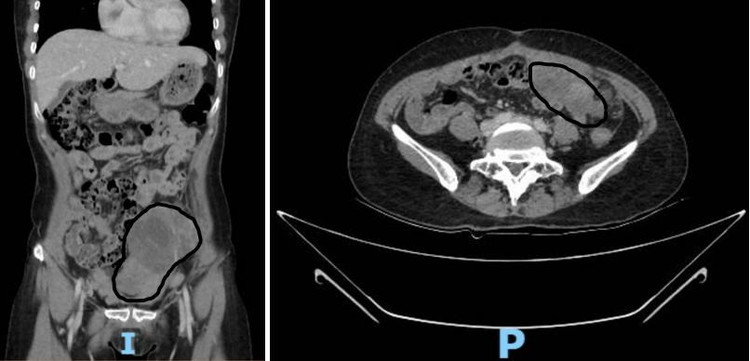

Đến năm 2024, bệnh nhân nhận thấy bụng to dần nên nhập viện tại Bệnh viện Ung Bướu TP Cần Thơ. Kết quả CT scan ghi nhận, khối tổn thương đậm độ mô mềm kích thước khoảng 150 x 102 mm và 81 x 52 mm, kèm dịch ổ bụng và thâm nhiễm mỡ mạc treo, gợi ý nhiều đến u ác tính buồng trứng di căn ổ bụng.

u-tai-phat.png

Hình 1. Hình ảnh khối u trên CTscan bụng theo các mặt cắt đứng dọc và ngang ghi nhận khối u ổ bụng rất to, giới hạn không rõ với các cơ quan khác - Ảnh BVCC